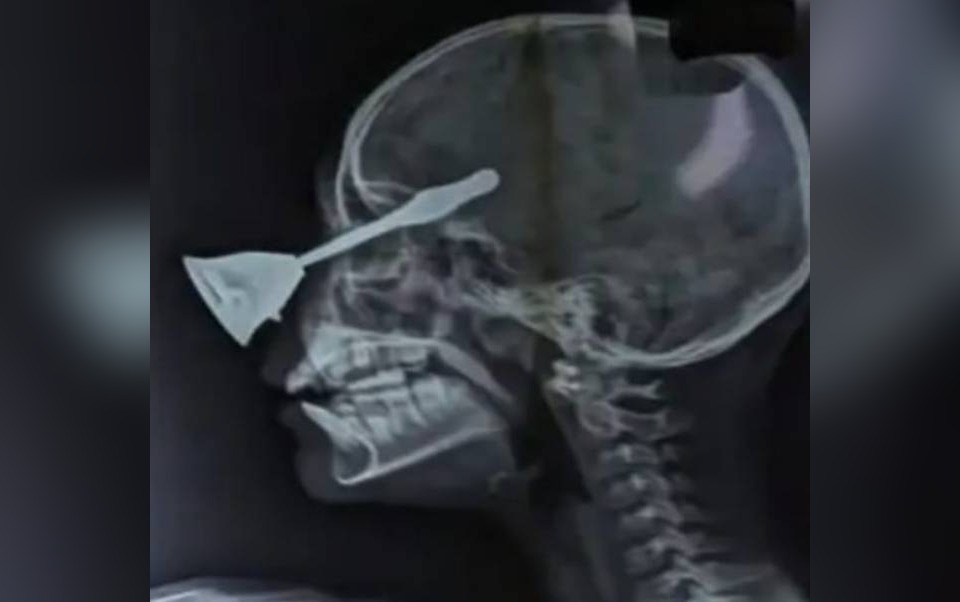

घंटी का पतला भाग बच्ची की आंख के आर-पार हुआ / (फोटो क्रेडिट : सोशल मीडिया)

छत्तीसगढ़ के बिलासपुर में दिवाली की रात 10 साल की एक बच्ची के साथ दर्दनाक हादसा हो गया. जब घर वाले दिवाली की पूजा कर रहे थे, उस दौरान एक मासूम बच्ची खेलते खेलते अचानक फिसल कर गिर गई. गिरते समय उसकी आंख में पूजा करने वाली घंटी घुस गईं, जो सीधे आंख को चीरते हुए दिमाग में घुस गई.

मस्तूरी निवासी दीपक सिंह अपने परिवार के साथ 20 अक्टूबर की रात पूजा कर रहेगा थे. जहां पर ही उनकी दस साल की बेटी काव्या सिंह खेल रही थी और इसी समय काव्या पूजास्थल के पास आकर खेलने लगी और अचानक ही उसका पैर फिसल गया. काव्या के गिरने पर नीचे रखी पूजा करने वाली घंटी आंख में घुस गई और देखते ही देखते दिवाली की खुशी गमगीन हो गई.

इस घटना से पूरे घर में हड़कंप मच गया. इसके बाद उसे नजदीक के अस्पताल में लाया गया, जहां से उसे सिम्स रेफर किया गया. सिम्स में उसकी हालत को देखते हुए तत्काल इलाज करते हुए एम्स रायपुर भेजा गया. एम्स में डॉक्टरों ने सर्जरी करके घंटी को निकाला है.

हालांकि, घंटी का सिरा मस्तिक तक पहुंच गया था, जिससे दिमाग पर असर पड़ा है, साथ ही काव्या एक आंख खराब हो गई है. काव्या का इलाज अभी भी चल रहा है और उसकी हालत में कोई सुधार नहीं देखने को मिला है.